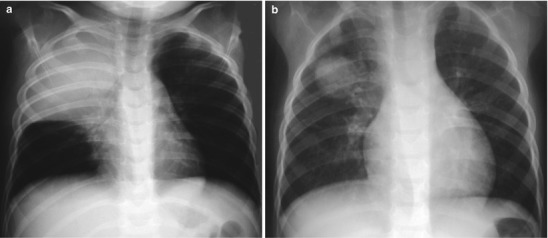

Chlamydia trachomatis is an obligate intracellular parasite. Genital chlamydial infection is recognized as the world’s most common sexually transmitted disease, and the high prevalence in women of childbearing age results in exposure of neonates during childbirth. Chlamydia pneumonia is a neonatal infection acquired after passage of the fetus through the cervix and vagina. The infant typically presents at 3–6 weeks of age with respiratory symptoms and occasional pulmonary hemorrhage. C. trachomatis should be suspected in infants who are afebrile or nontoxic and have a dry cough. These patients often have a peripheral eosinophilic pleocytosis, sometimes with concomitant conjunctivitis (Ostapchuk et al. 2004). Most chest radiographs show bilateral hyperaeration and diffuse infiltrates with a variety of radiographic patterns including interstitial, reticular nodular, atelectasis, coalescence, and bronchopneumonia (Radkowski et al. 1981) (Fig. 13.16).

Fig. 13.16.

Chlamydia pneumonia. Radiograph of an afebrile 2-week-old girl with dry cough shows bilateral hyperaeration and diffuse interstitial infiltrates, appearing coalescent on the right